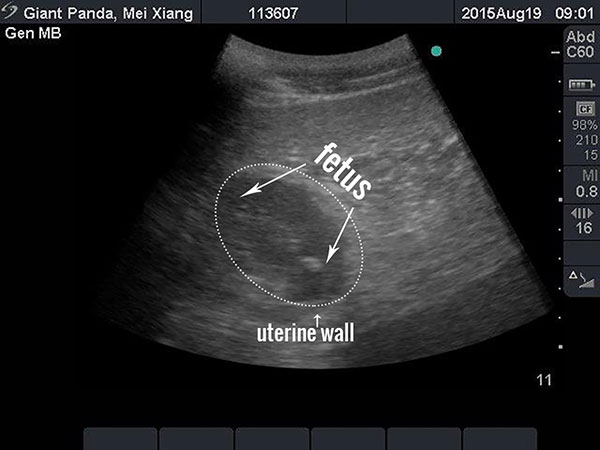

An ultrasound image of the National Zoo's giant panda Mei Xiang is pictured in this handout photograph taken and released on August 19, 2015. Mei Xiang is believed to be carrying a developing fetus and could give birth in coming weeks, the Washington zoo said on Wednesday, August 12, 2015. Veterinarians detected a 1.6-inch (4-cm) fetus during a Wednesday ultrasound, the zoo said in a statement. [Photo/Agencies]